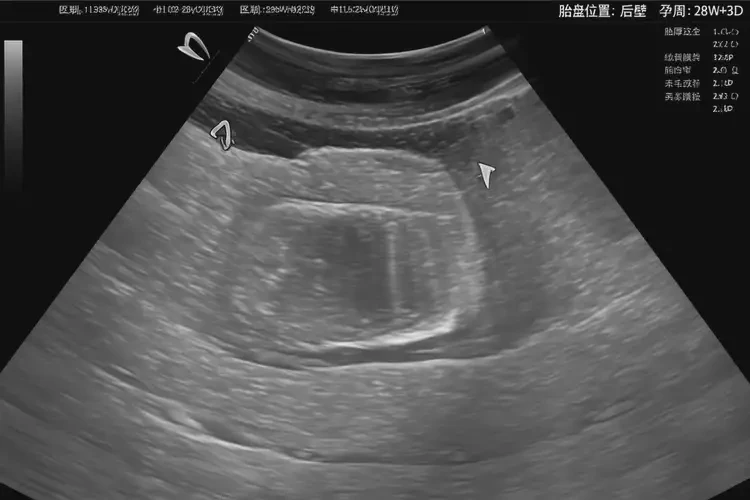

懷孕11周胎心80怎么回事(圖1)

1. 超聲檢查

• 胎兒心臟超聲:可以詳細(xì)評估胎兒心臟結(jié)構(gòu)和功能,確定是否存在心臟畸形或其他異常。

• 胎盤超聲:可以評估胎盤位置、形態(tài)和功能,確定是否存在胎盤早剝或前置胎盤等問題。